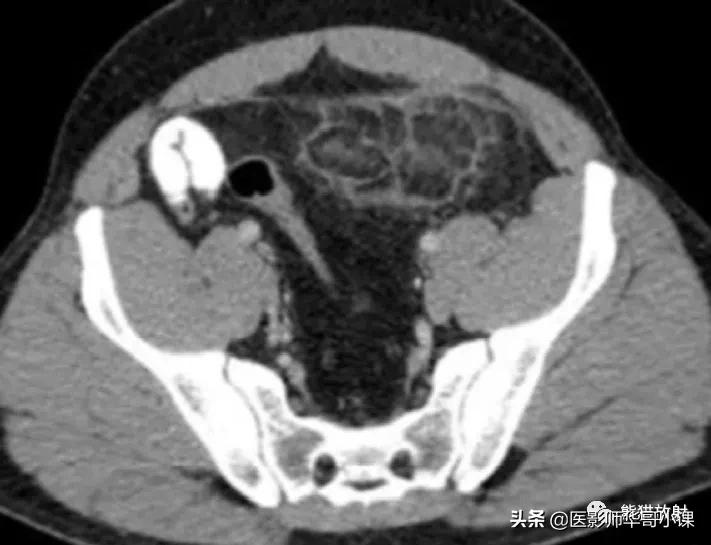

节段性网膜梗死是 引起急性腹痛的少见疾病 ,是由于大网膜血管损害所致。原发性网膜扭转,由于先天性或血管的变异,易形成静脉内血栓,多发生于右侧。肥胖尤其被推测为重要的危险因素。继发性网膜梗死与之前的腹部病变有关,包括手术、腹部炎症病灶、肿瘤、疝囊等,梗死灶位于原发病变附近, 典型CT表现 为单个较大的密度不均的网膜肿块, 内含条带状高密度影 ,常位于右下腹(图)。肿块常常 大于5cm ,由此和肠脂垂炎相鉴别。本病恰当的治疗是非手术治疗。

左侧网膜梗死。增强CT显示一个直接约8cm的不均匀脂肪密度灶,位于左侧腹直肌及壁层腹膜深处,并周围炎症。